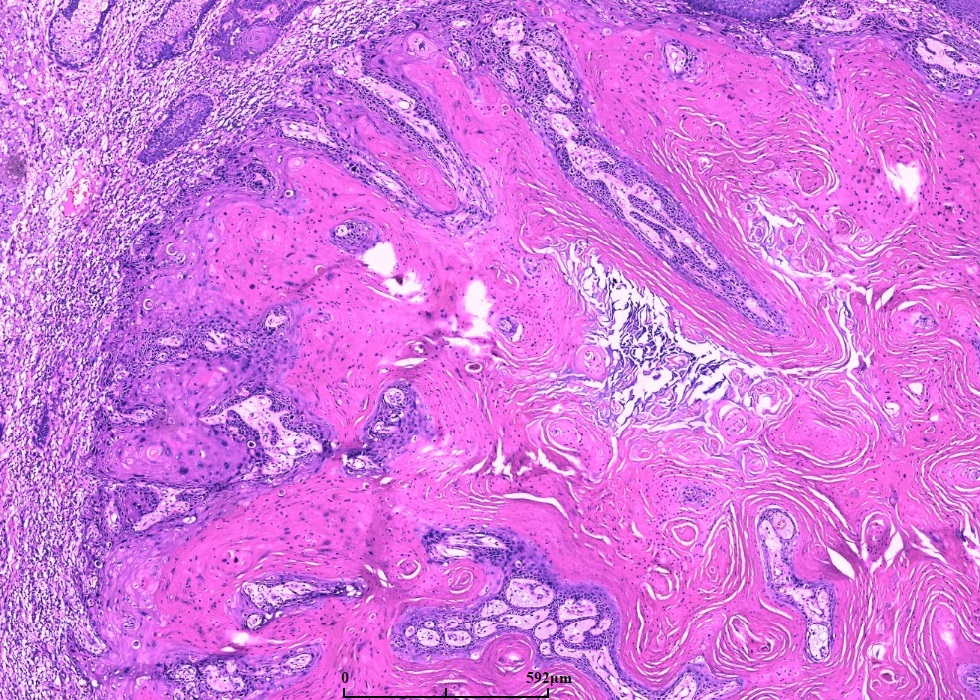

早期呈界限清楚的由大的鳞状上皮构成的实性叶状结构,角化少,细胞异型轻微;

随着病变进展,中央出现火山样结构,内含角化细胞及角化物,无颗粒细胞;

鳞状上皮巢不规则向深部浸润,但轮廓光滑,一般不会超过附属器的水平,深部的上皮细胞巢或上皮脚顶端可出现角化珠和上皮内中性粒细胞微脓肿;

角质形成细胞胞质丰富、强嗜酸性,细胞异型程度不等,但通常较轻且局限于基底细胞层;